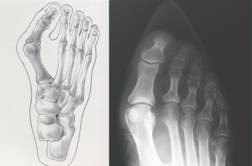

好發於老年人的腳拇指外翻,隨著女性高跟尖頭鞋流行,不少年輕「美眉」為拇指外翻所苦,有人外翻角度直逼六十度,得動刀解除痛苦;骨科專業醫師表示, 建議女性穿尖頭鞋加裝墊片,分散拇指壓力。

腳拇指外翻是指大拇指的骨頭向外側翻,嚴重的話,影響第二指,甚至第三指,患者一穿鞋,腳指摩擦,痛到無法走路,得開刀解決。

腳拇指外翻男女有別,男性多屬運動傷害造成,女性則和高跟、尖頭鞋有關,當然,走路姿勢不正確,也可能導致拇指外翻,但是,近來多起腳拇指外翻的女性患者,和穿著高跟的尖頭鞋有關。

建議女性朋友,非得穿著尖頭鞋不可,不妨在鞋子加裝墊片,避免走路時,壓力集中腳拇指,導致拇指變形。夜間睡眠時建議可使用拇指外翻矯正器,如此至少可以避免更嚴重的惡化產生。